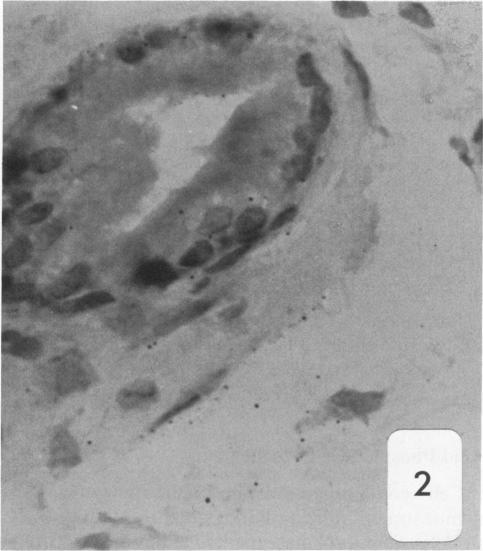

Dunning R3327-H rat prostate adenocarcinoma cells, when grown in syngeneic (Copenhagen) rats or nude mice, produce tumors with prominent hypercellular stroma. The authors have previously demonstrated the presence of anomalous steroid-sensitive cells in both the epithelium and stromal compartments of this model system. In order to better understand the histogenesis of these cells, the authors studied samples of the tumor which were radiolabeled overnight with tritiated dihydrotestosterone (3H-DHT). Frozen sections of the tissues were thaw-mounted onto autoradiographic emulsion-coated slides to permit silver grain identification in association with nuclei of androgen-sensitive cells. Surprisingly, numerous silver grains were found to be associated with nuclei of large cells within the stroma. Therefore, these cells were termed "epithelioid" pending confirmation of their origin. To further define these cells and their relationship to the surrounding matrix, autoradiograms have now been examined immunohistochemically with antibodies directed against the basement membrane glycoprotein, laminin, as well as antibodies specific for intermediate cytoskeletal filaments. Following identification of acinar basement membranes, epithelioid cells were identifiable both in the stroma and in the acinar epithelial cell layer. Histochemical staining with acid phosphatase, a marker for prostatic epithelium, was performed and shown to be present in acinar epithelial cells as well as in epithelioid cells. Additionally, fluorescence-activated cell sorting was employed to characterize the DNA content of cell types within the H tumor. Epithelioid cells were found to be in highest concentration in an aneuploid peak with a ploidy of approximately 6N. The autoradiographic, immunohistochemical, cytometric, and ultramicroscopic studies suggest that 1) epithelioid cells are epithelial derived stromal cells; 2) these epithelioid cells arise by pathologic division of aneuploid neoplastic precursor cells of approximately 3N ploidy, which are found within the prostatic epithelium; and 3) the resulting 6N cells degrade the basement membrane locally, invade the stroma, and populate it. Here, they can be distinguished from fibroblasts by their size, acid phosphatase activity, and hormone receptor content. Thus, the term "epithelioid" is inappropriate; and these cells should be regarded simply as large neoplastic epithelial (LNE) cells. The presence of this cell type suggests that this tumor subline represents a useful naturally occurring model for the study of the initial stages of neoplastic transformation.

邓宁R3327 - H大鼠前列腺腺癌细胞在同基因(哥本哈根)大鼠或裸鼠体内生长时,会产生具有显著细胞增多性基质的肿瘤。作者此前已证明在该模型系统的上皮和基质区室中均存在异常的类固醇敏感细胞。为了更好地理解这些细胞的组织发生,作者研究了用氚化双氢睾酮(3H - DHT)过夜进行放射性标记的肿瘤样本。将组织的冰冻切片解冻后贴在涂有放射自显影乳剂的载玻片上,以便确定与雄激素敏感细胞核相关的银颗粒。令人惊讶的是,发现大量银颗粒与基质内大细胞的核相关。因此,在确认其起源之前,这些细胞被称为“上皮样细胞”。为了进一步定义这些细胞及其与周围基质的关系,现在已用针对基底膜糖蛋白层粘连蛋白的抗体以及针对中间细胞骨架丝的特异性抗体对放射自显影片进行免疫组织化学检查。在确定腺泡基底膜后,在上皮样细胞的基质和腺泡上皮细胞层中均可识别出上皮样细胞。用酸性磷酸酶进行组织化学染色,酸性磷酸酶是前列腺上皮的标志物,结果显示其存在于腺泡上皮细胞以及上皮样细胞中。此外,采用荧光激活细胞分选技术来表征H肿瘤内细胞类型的DNA含量。发现上皮样细胞在非整倍体峰中浓度最高,其倍性约为6N。放射自显影、免疫组织化学、细胞计量学和超微结构研究表明:1)上皮样细胞是上皮来源的基质细胞;2)这些上皮样细胞由前列腺上皮内约3N倍性的非整倍体肿瘤前体细胞的病理性分裂产生;3)产生的6N细胞局部降解基底膜,侵入基质并在其中聚集。在这里,它们可以通过大小、酸性磷酸酶活性和激素受体含量与成纤维细胞区分开来。因此,“上皮样”这个术语并不恰当;这些细胞应简单地视为大肿瘤上皮(LNE)细胞。这种细胞类型的存在表明该肿瘤亚系是研究肿瘤转化初始阶段的一个有用的自然发生模型。